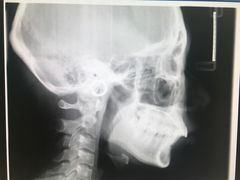

• 固瑞齿科(国贸门诊店)

• -固瑞齿科(国贸门诊店)